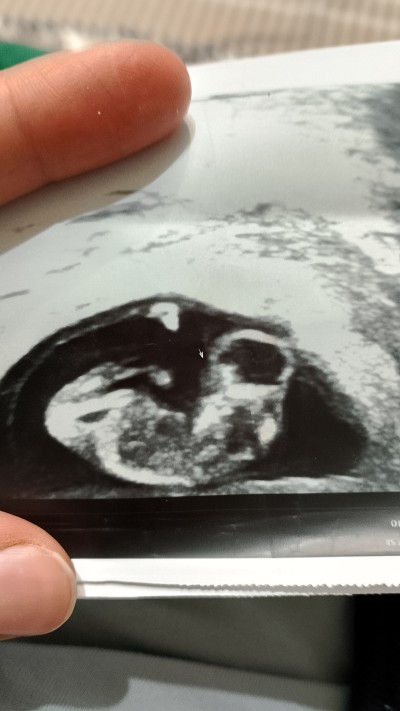

11+4 haftalık hamileyim bugün ultrasonumda bebeğimin baş kısmında bir kitle olduğu söylendi ve bu bir sakatlık türüymüş kürtaj olmazsam bile zaman içinde anne karninda ölür dediler bu durumu yaşıyan ve atlatan varmı doğruluk oranı nedir lütfen dualarınızı eksik etmeyin

Gebelik haftası 11+4

Hayır sadece baş ve boyun arasında bir kitle var dediler